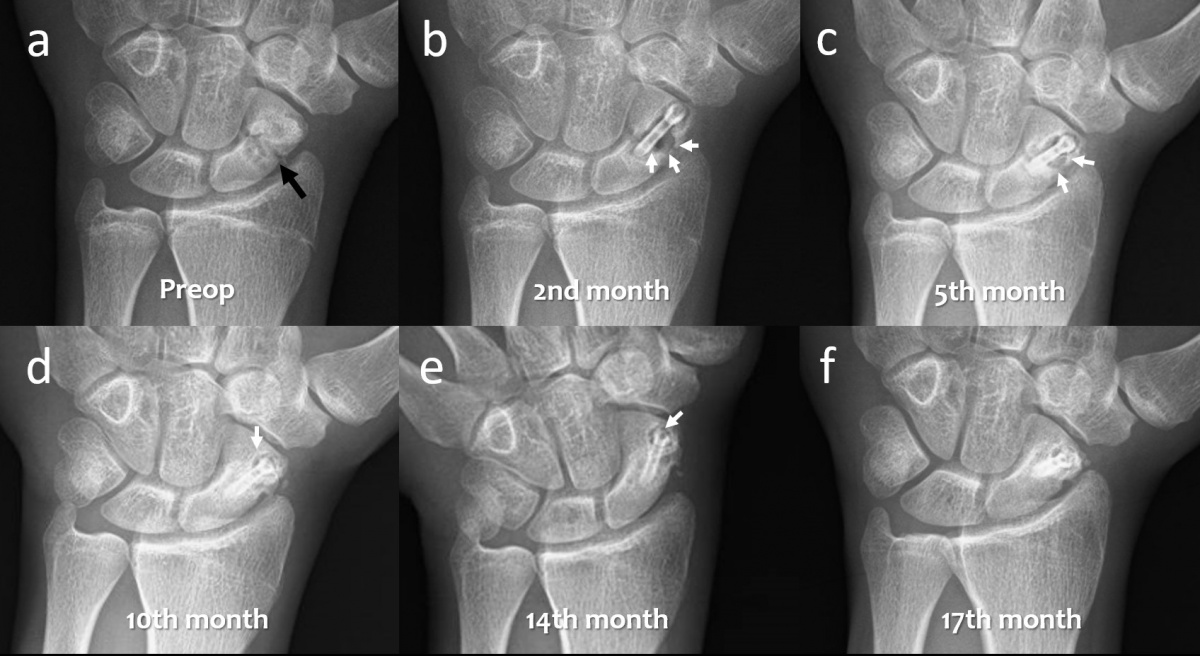

mit Kahnbeinpseudoarthrose, die mit Magnesiumschrauben fixiert wurde. (a) Präoperative

posterior-anteriore (pa) Röntgenaufnahme des Handgelenks mit sichtbarer Kahnbeinpseudoarthrose

(schwarzer Pfeil). (b-f) Serielle pa-Röntgenaufnahmen des Handgelenks zeigen die allmähliche

Resorption der Gasansammlung im Knochen bei der Nachbeobachtung 2, 5, 10, 14 und 17

Monate postoperativ. Bemerkenswert: die Heilung und Konsolidierung der Pseudoarthrose.

Neben diesen positiven Ergebnissen wurden in zwei Studien auch negative Ergebnisse berichtet (24, 25). In der ersten Studie wurde an der Hand eine Fusion von Skaphoid, Trapezium und Trapezoideum (STT) mit zwei Magnesiumschrauben an einem 42-jährigen Patienten nach Kahnbeinfraktur und SST-Arthrose vorgenommen. In der Frühphase kam es zu beträchtlicher Gasbildung. Zudem wurden eine Lockerung der Implantate und eine „Zystenbildung“ innerhalb der Karpalknochen festgestellt, sodass der Patient einer Revision unterzogen wurde (24). U.E. war der Operationsmisserfolg vorhersehbar, da ganz offensichtlich mehrere Kontraindikationen nicht beachtet worden waren. Als weiteres negatives Ergebnis wurde bei der Fixierung von fünf akuten Kahnbeinfrakturen berichtet. Wie auch im vorherigen Bericht sahen die Autoren in der frühen postoperativen Phase eine beträchtliche Gasbildung um die Schrauben herum und bewerteten diese Phänomene als „Osteolyse“ und somit als Misserfolg der Operation. Bei der klinischen und radiologischen Nachbeobachtung waren die klinischen Ergebnisse jedoch hervorragend: alle Patienten erreichten durchschnittlich 99 Punkte im Mayo-Wrist-Score und es wurde keine non-union oder Pseudoarthrose festgestellt (25). Zumindest in der letzten Fallserie war ganz offensichtlich eine Fehlinterpretation der im vorhergehenden Abschnitt beschriebenen spezifischen Aufnahmen der Grund für das schlechte Fazit. Dies unterstreicht die Bedeutung einer korrekten Bewertung von radiologischen Befunden während der Degradationsphase. Chirurgen, die solche Implantate verwenden, sollten somit in der Lage sein, diese Aufnahmen korrekt zu beurteilen und mit dem Korrosionsprozess von Mg-basierten Biomaterialien vertraut sein.